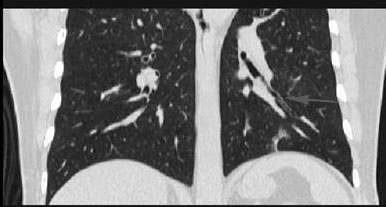

大体病理所见:左肺下叶外基底段实变,由远至近分多刀横切不张之肺实质,肺段内支气管扩张,扩张之支气管内显示大量脓性粘液溢出,基底干支气管远端见直径0.8cm的结节,向下延伸至外基底段支气管内,呈长条状结构,前内、后基底段支气管开口狭窄。

下图箭头所指为阻塞后充满粘液的扩张支气管1

该病例提示我们熟悉胸部断面解剖、特别是支气管断面解剖对诊断肺内病变的重要性